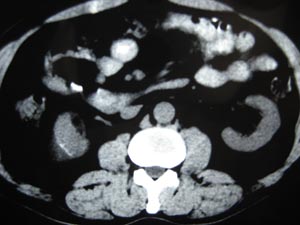

标题: CT17067:男,50Y右上腹痛一个月,无外伤史 [打印本页]

标题: CT17067:男,50Y右上腹痛一个月,无外伤史

右肾包膜下积液,包膜可见线状钙化

不除外慢性血肿

右肾包膜下积液(陈旧性血肿?),包膜可见线状钙化。

右肾包膜下积液,包膜可见线状钙化。左肾可疑血管平滑肌脂肪瘤,把窗调宽一些.